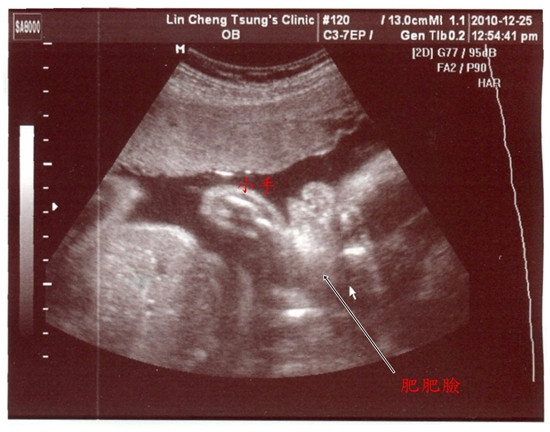

99.12.25這一天我們進行27W的例行產檢

在林醫師這邊產檢...每次都會照使用高層次超音波來檢查寶寶

因為解析度高...所以用來檢查與判斷器官的成長狀況

才一個月不見...肚子裡的寶貝已經使長肉肉囉!

整個臉肥嘟嘟的...寶寶長大了快一倍...已經1.3KG囉!

我把林小兔養的真好...除了長太大以外...其他的檢查都正常

林小兔27W產檢~高層次超音波與4D超音波清晰度比一比